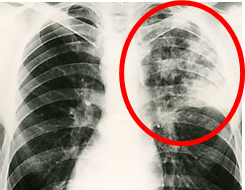

. 흉부 방사선 사진

◈ 결핵 치료를 받은 적이 없는데 흉부 사진에 결핵 흉터가 있는 경우?

. 결핵이 면역기 전에 의해 자연 치료된 경우 흉터가 흉부 사진에 남기도 한다.

. 흉부 방사선 사진만으로는 명확하게 구분이 어려운 경우가 많다.